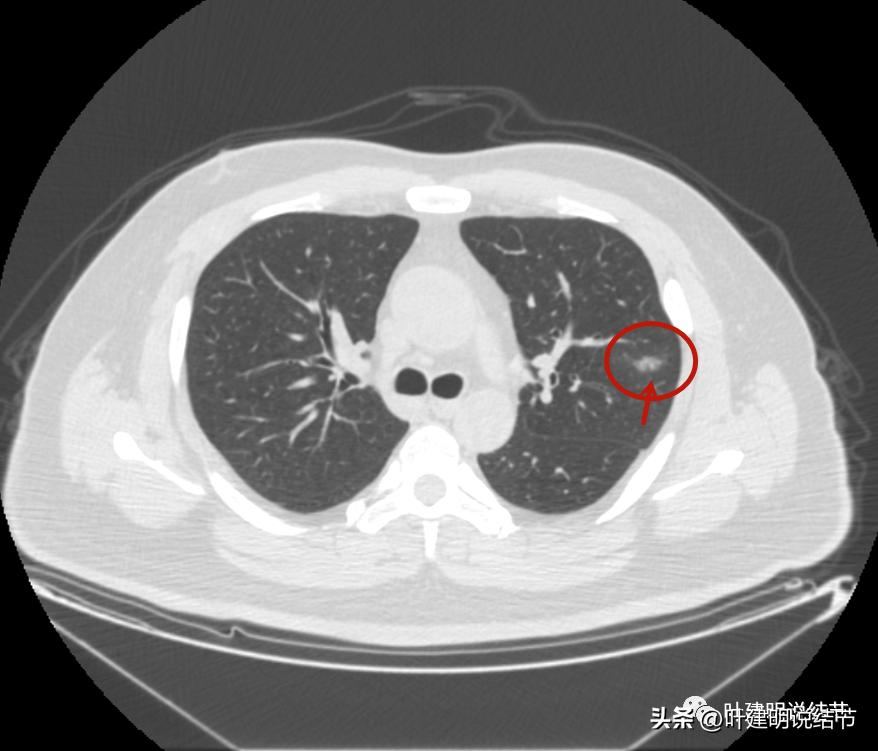

后续再看2022年8月的CT图像,有点惊掉下巴的感觉:

左上叶的病灶1、2、3都没有了!!!完全没有了!那当然说明是炎症性的,居然全部吸收了!

但左上病灶4仍在,形态也没有明显变化,无好转,也无明显进展。这是肿瘤性质的吗?虽然存在2年多了,但因为它的兄弟们都不见了,让我对它认定的肿瘤范畴也产生了怀疑,也许是纤维增生而已呢!